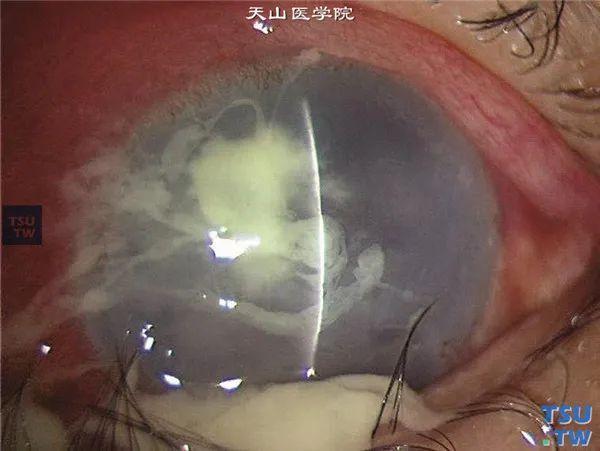

史院长在采访中提到的戴隐形可能导致阿米巴虫感染,就是指棘阿米巴角膜炎(图一)。棘阿米巴和人经常接触,一般不致病,但一定条件下则致病。而戴隐形眼镜的人,由于泪液循环受影响、配戴时长过长、干眼症等原因,角膜上皮容易出现微损伤,就给棘阿米巴虫创造了致病条件。国外一所医院其21年所有棘阿米巴角膜炎的患者,93.2%的都使用了隐形眼镜。

左右滑动查看图一